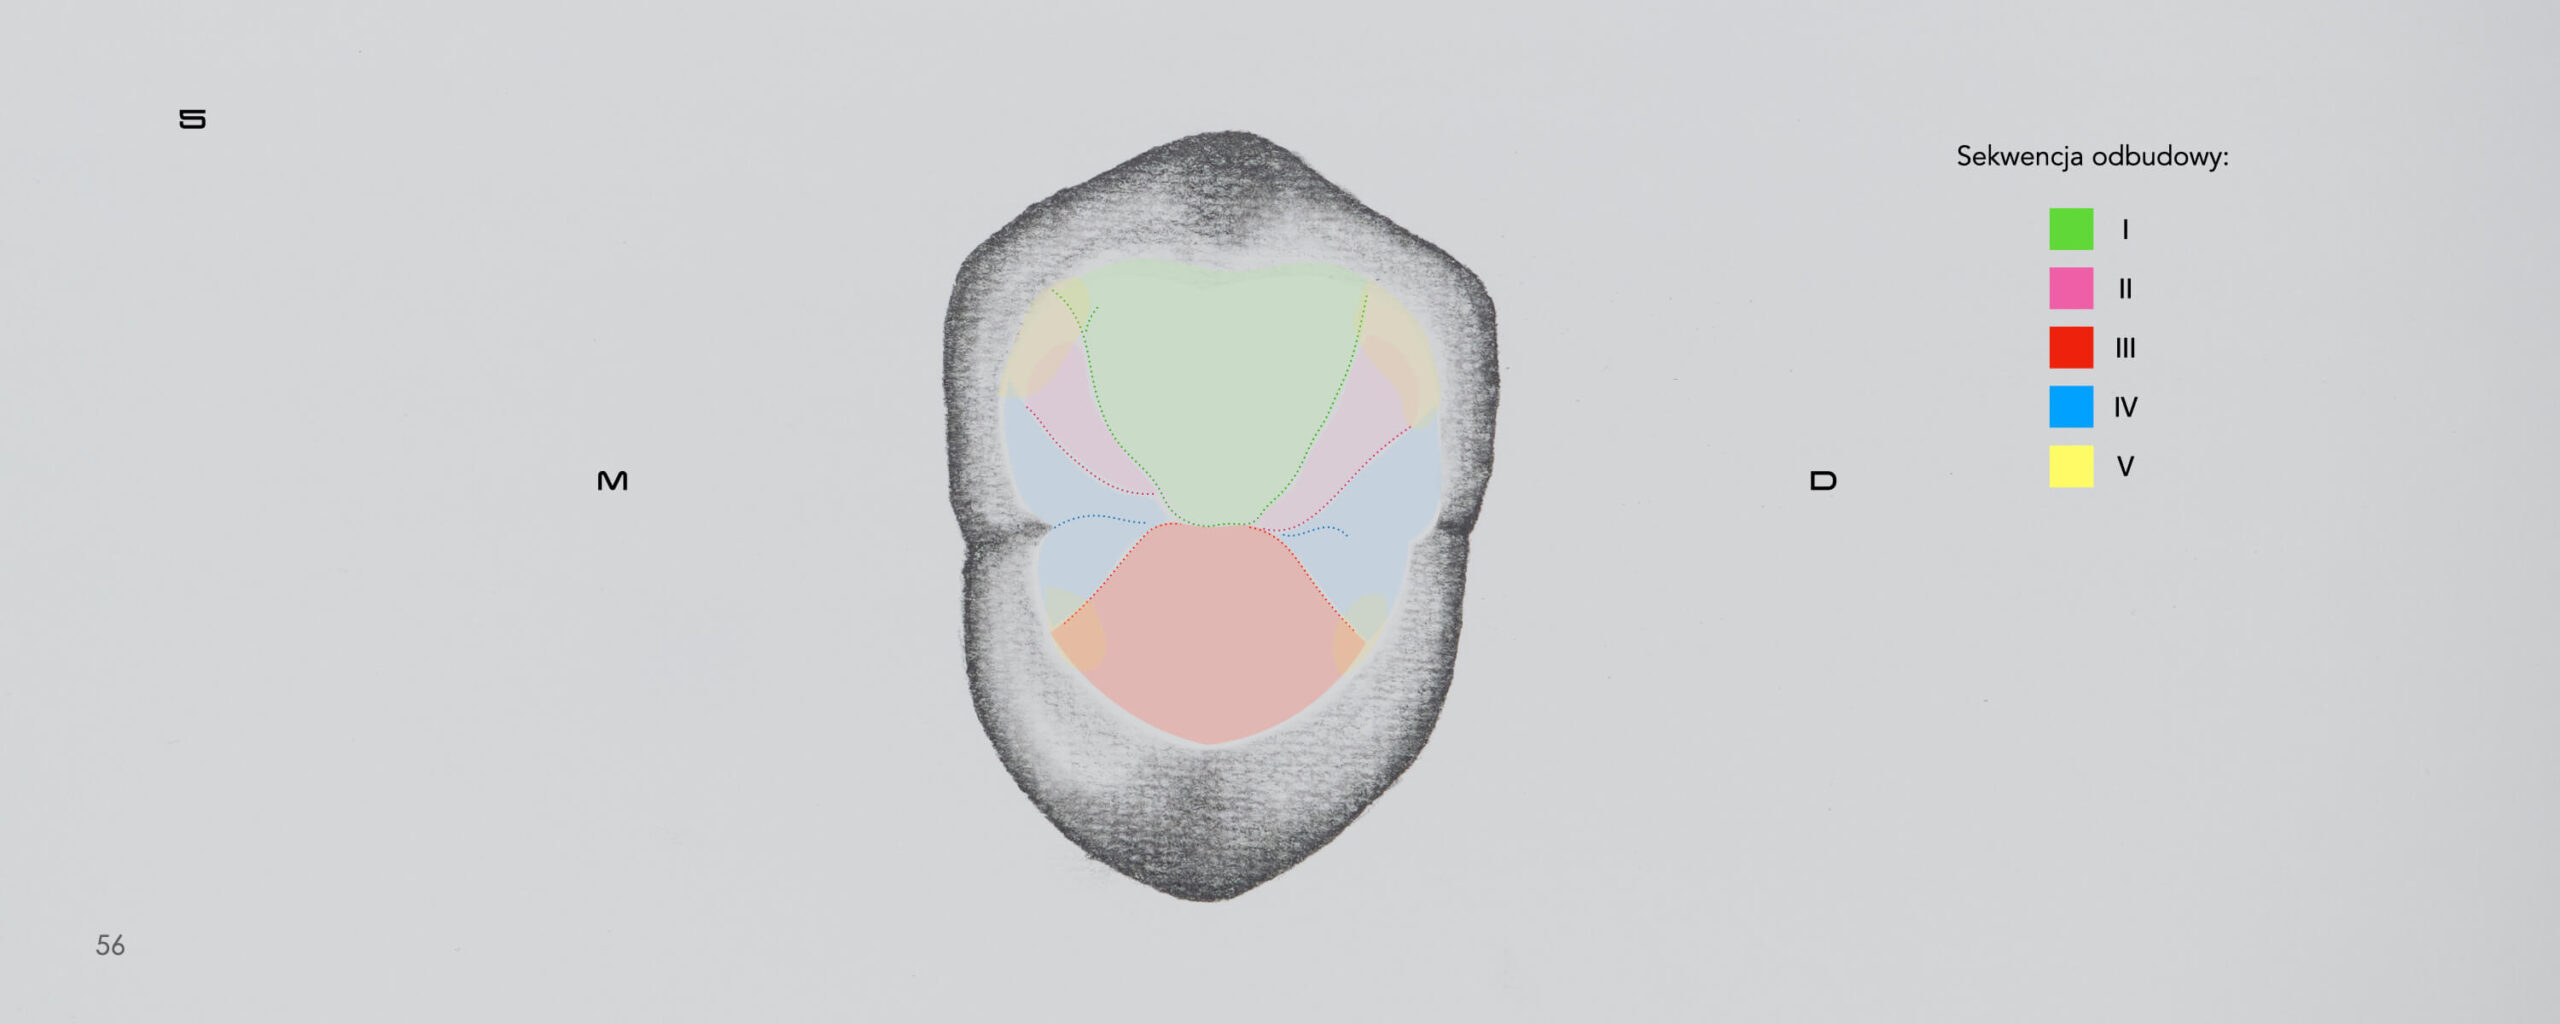

Posterior Teeth Morphology

Direct Composite Restorations

What does the anatomy of natural teeth look like?

Does the shape of the cusps matter?

Is there a scheme to work with?

How to characterize the occlusal surface to emphasize the

natural effect?

You’ll find the answers to this and more. After reading this atlas, you will be prepared how to create the biomimetic